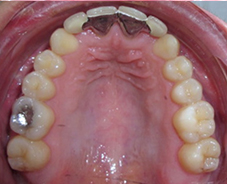

Photo 1 : Arcade maxillaire après traitement orthodontique, agénésie des incisives latérales maxillaires

Photo 2 : Bridge collé en cantilever, piliers de bridge 11-21